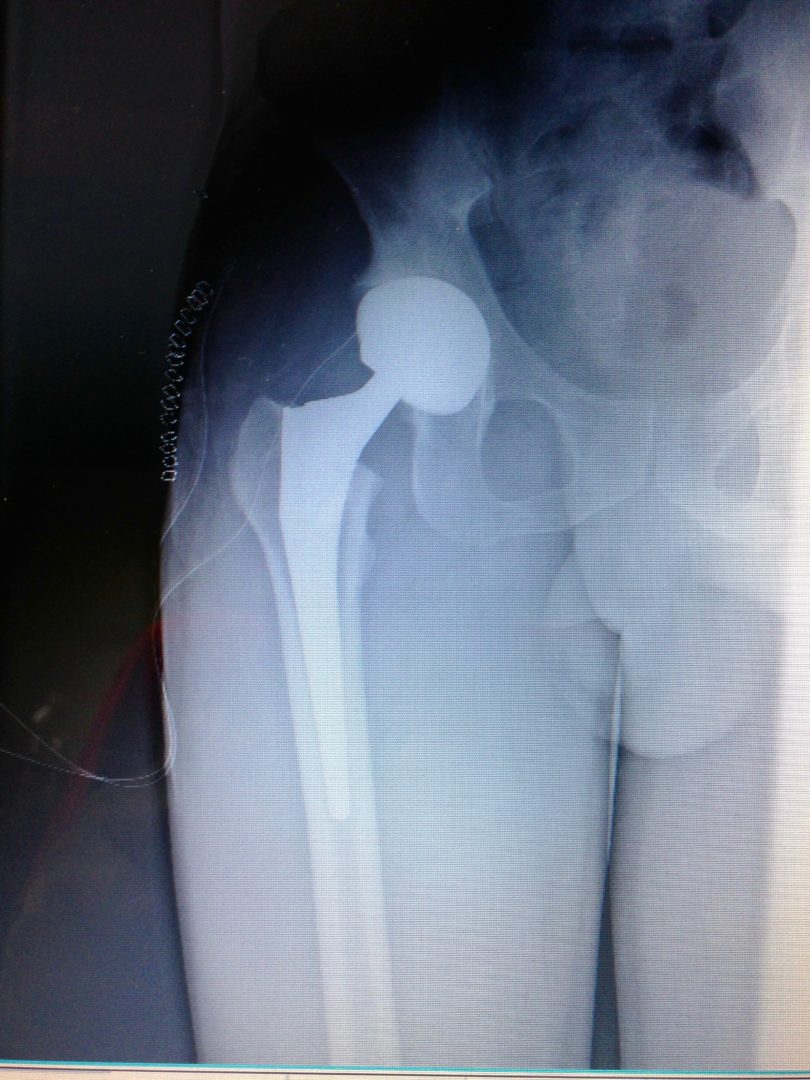

C’est vers le milieu du 20ème siècle que la forme que nous connaissons aux prothèses articulaires actuellement a été fixée. La principale révolution a eu lieu au niveau de la hanche et provient de deux chirurgiens orthopédistes : le Suisse Maurice-Étienne Müller de Berne et le Britannique Sir John Charnley. Ils ont conçu une prothèse articulaire transformant une hanche naturelle qui relie une grosse tête de fémur (pouvant aller de 44 mm à 62 mm) et un cotyle, en une tête métallique de 22 ou 28 mm portée par une tige scellée dans le fémur et articulée avec une cupule en polyéthylène PE (cf. infra) scellée dans le bassin : c’est le concept du Low Friction torque Arthroplasty (LFA), autrement dit le couple de faible friction tribologique. En effet, jusque dans ces années 1960, les prothèses tâchaient de reproduire tout bonnement la hanche naturelle telle quelle. La conséquence est une faible épaisseur de PE dans le cotyle prothésé, or nous n’étions pas encore à l’époque du PE de haute densité comme aujourd’hui. Le résultat est une usure rapide de la cupule en PE (qui est littéralement laminée par la tête prothétique) avec relargage des particules de polyéthylène responsables d’une réaction de la part des cellules de défense de l’organisme aboutissant à un descellement de la prothèse. C’est également au début de ces années 60 que le ciment acrylique a été introduit. C’est du poly méthyl méta acrylate qui, en se polymérisant devient dur et permet de sceller les implants dans l’os. Le prix à payer pour ce modèle de « petite tête fémorale » dans une « petite cupule cotyloïdienne » est l’instabilité avec des luxations. Pour y pallier, des cupules dites rétentives ont été introduites avec comme conséquence, l’augmentation des contraintes sur le PE dont le corollaire est l’usure – descellement. Jusque dans les années 90, la durée de vie des prothèses était autour de 10 ans.

Actuellement, l’amélioration de la qualité des matériaux ainsi que de leur usinage, surtout le polissage de la surface de friction, ont permis de porter la durée de vie des prothèses au-delà de 30 ans. Trois catégories de matériaux sont actuellement utilisées. Il s’agit des alliages métalliques, des céramiques et du polyéthylène de haute densité. Des essais d’implants en carbone sont en cours.

Les alliages métalliques sont essentiellement en chrome – cobalt et en titane. Les céramiques sont des matériaux non métalliques et non organiques obtenus par l’effet de fortes températures sur de l’alumine ou du zircon. Le polyéthylène est un matériau plastique issu de l’industrie pétrochimique. Il sert à constituer la surface de friction des implants. L’introduction du ciment acrylique dans la fixation des implants à l’os date du début des années 60. Depuis le milieu des années 80, le concept de prothèse sans ciment est apparu. Le principe consiste à recouvrir la surface de contact des implants avec l’os d’un revêtement dit ostéo-conducteur. Il s’agit de l’hydroxyapatite, un composant minéral naturel de l’os que l’on produit artificiellement. Au contact de la prothèse, l’os du voisinage identifie cet hydroxyapatite comme un de ses propres constituants et le colonise. La prothèse devient ainsi intégrée à l’os. On parle alors de stabilité secondaire. Naturellement, en attendant cette repousse d’os sur le revêtement d’hydroxyapatite, la stabilité primaire est assurée par l’impaction en force de la prothèse dans l’os et éventuellement fixée par des vis complémentaires. Les couples de friction (surface de frottement des implants) sont de plusieurs sortes : métal – PE, céramique – PE, céramique – céramique. Le couple métal – métal dit de gros diamètre a été utilisé au moins durant trois périodes depuis le 20ème siècle dont la dernière au-début des années 2000 avant d’être à nouveau abandonné pour cause de relargage excessif de particules de métal dans l’organisme.

Pour finir, il faut savoir que les systèmes de détection des métaux au niveau des portiques de sécurité (aéroports, lieux sensibles…) sont de plus en plus sensibles à la quantité de métal détectable. Il faut penser à avoir sur soi un certificat médical et ou le compte rendu opératoire lors des passages lorsque l’on a été opéré d’une prothèse articulaire.